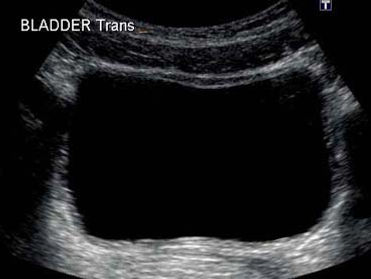

Bladder Ultrasound

Bladder ultrasound is done with a full bladder to evaluate the walls and volume of the bladder. After voiding, the bladder is reassessed to see if there is any postvoid residual. More INFO>>>